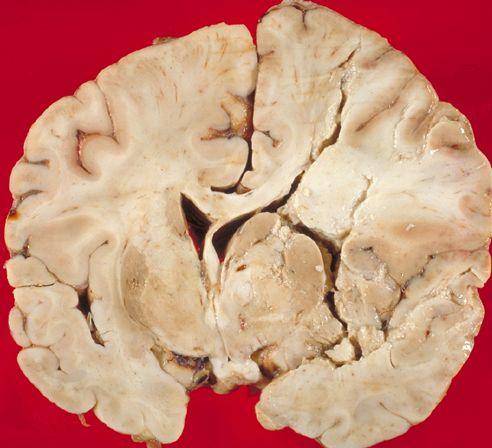

Cum arată CREIERUL UMAN după un ATAC CEREBRAL

Foto: neuropathology-web.org